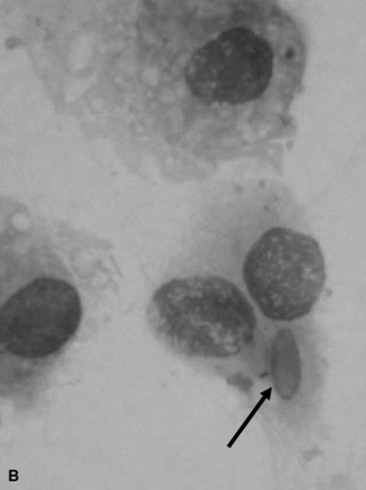

Fungal pneumonia may be diagnosed from samples obtained by tracheal wash or BAL or via a lung biopsy (Fig. 31-17). Lung biopsy is associated with significant risk if a pulmonary vessel is accidentally biopsied. The biopsy should be performed ideally after radiographic evaluation or with concurrent ultrasound guidance, and the sample should be obtained from the periphery of the lung; however, some horses have experienced fatal hemorrhage associated with biopsy of a vessel only 2 cm from the periphery. The lung is rich in plasminogen, so bleeding complications may be severe. Spring-loaded biopsy needles are safer for lung biopsy than Tru-Cut biopsy instruments.324 Ultrasound evaluation can be used to monitor for bleeding after the procedure.

image

Fig. 31-17 Percutaneous lung biopsy from caudal periphery of lung of a weanling foal.